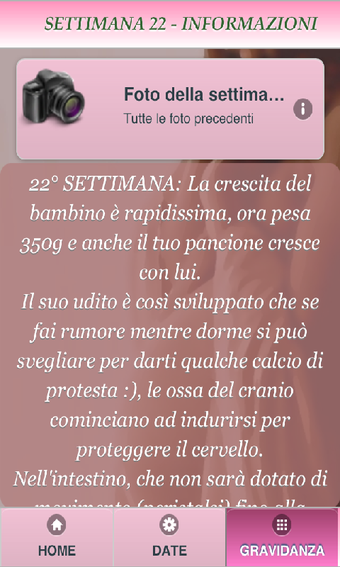

Each week, the mother can access a detailed description of the child's development, with a description of the changes that are taking place in her body.

This week, there are some messages that are specific for the current stage of development of the child.